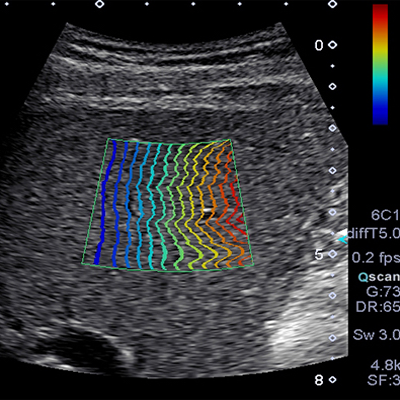

L’élastographie (Shearwave) est une technique récente de l’échographie. Elle étudie les propriétés élastiques et la rigidité des tissus biologiques.

Dans cette modalité d’imagerie, nous étudions la vitesse de propagation d’une onde de cisaillement au sein des structures. Une cartographie relative à l’élasticité des tissus examinés est générée.

Le postulat de départ est que les lésions cancéreuses présentent souvent une rigidité supérieure aux lésions bénignes. Ceci n’est pas toutefois pas vérifié de façon systématique.

L’élastographie permet donc dans certains cas d’apporter des informations diagnostiques supplémentaires et d’améliorer la caractérisation des lésions.

Nos échographes sont équipés de la technique la plus récente, par onde de cisaillement. Cette onde est directement générée par la sonde d’échographie. Elle se propage de façon parallèle aux plans cutanés. Sa vitesse de déplacement ne dépend pas de la pression exercée par le médecin. Il s’agit d’une technique reproductible.